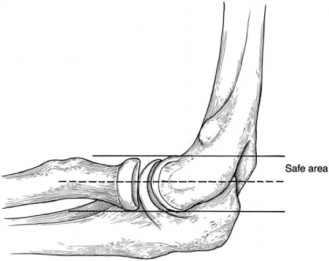

The correct answer is (C). Nonoperative treatment of SC joint osteoarthritis is the mainstay of initial treatment, and most symptomatic patients will respond to these nonsurgical treatments. The other conservative treatment options listed are incorrect in this case because they would be less likely to result in symptom relief. Answer D is incorrect because conservative measures should be attempted for at least 6 months before operative treatment is considered. When performing intra-articular injections under CT guidance, the clinician should have clear knowledge of the surrounding anatomy. Figure 2–74 demonstrates the relationships of the surrounding anatomy.

Figure 2–74_Reproduced with permission from Higginbotham TO, Kuhn JE. Atraumatic discorders of the sternoclavicular joint. _J Am Acad Orthop Surg 2005;13(2):138–145.